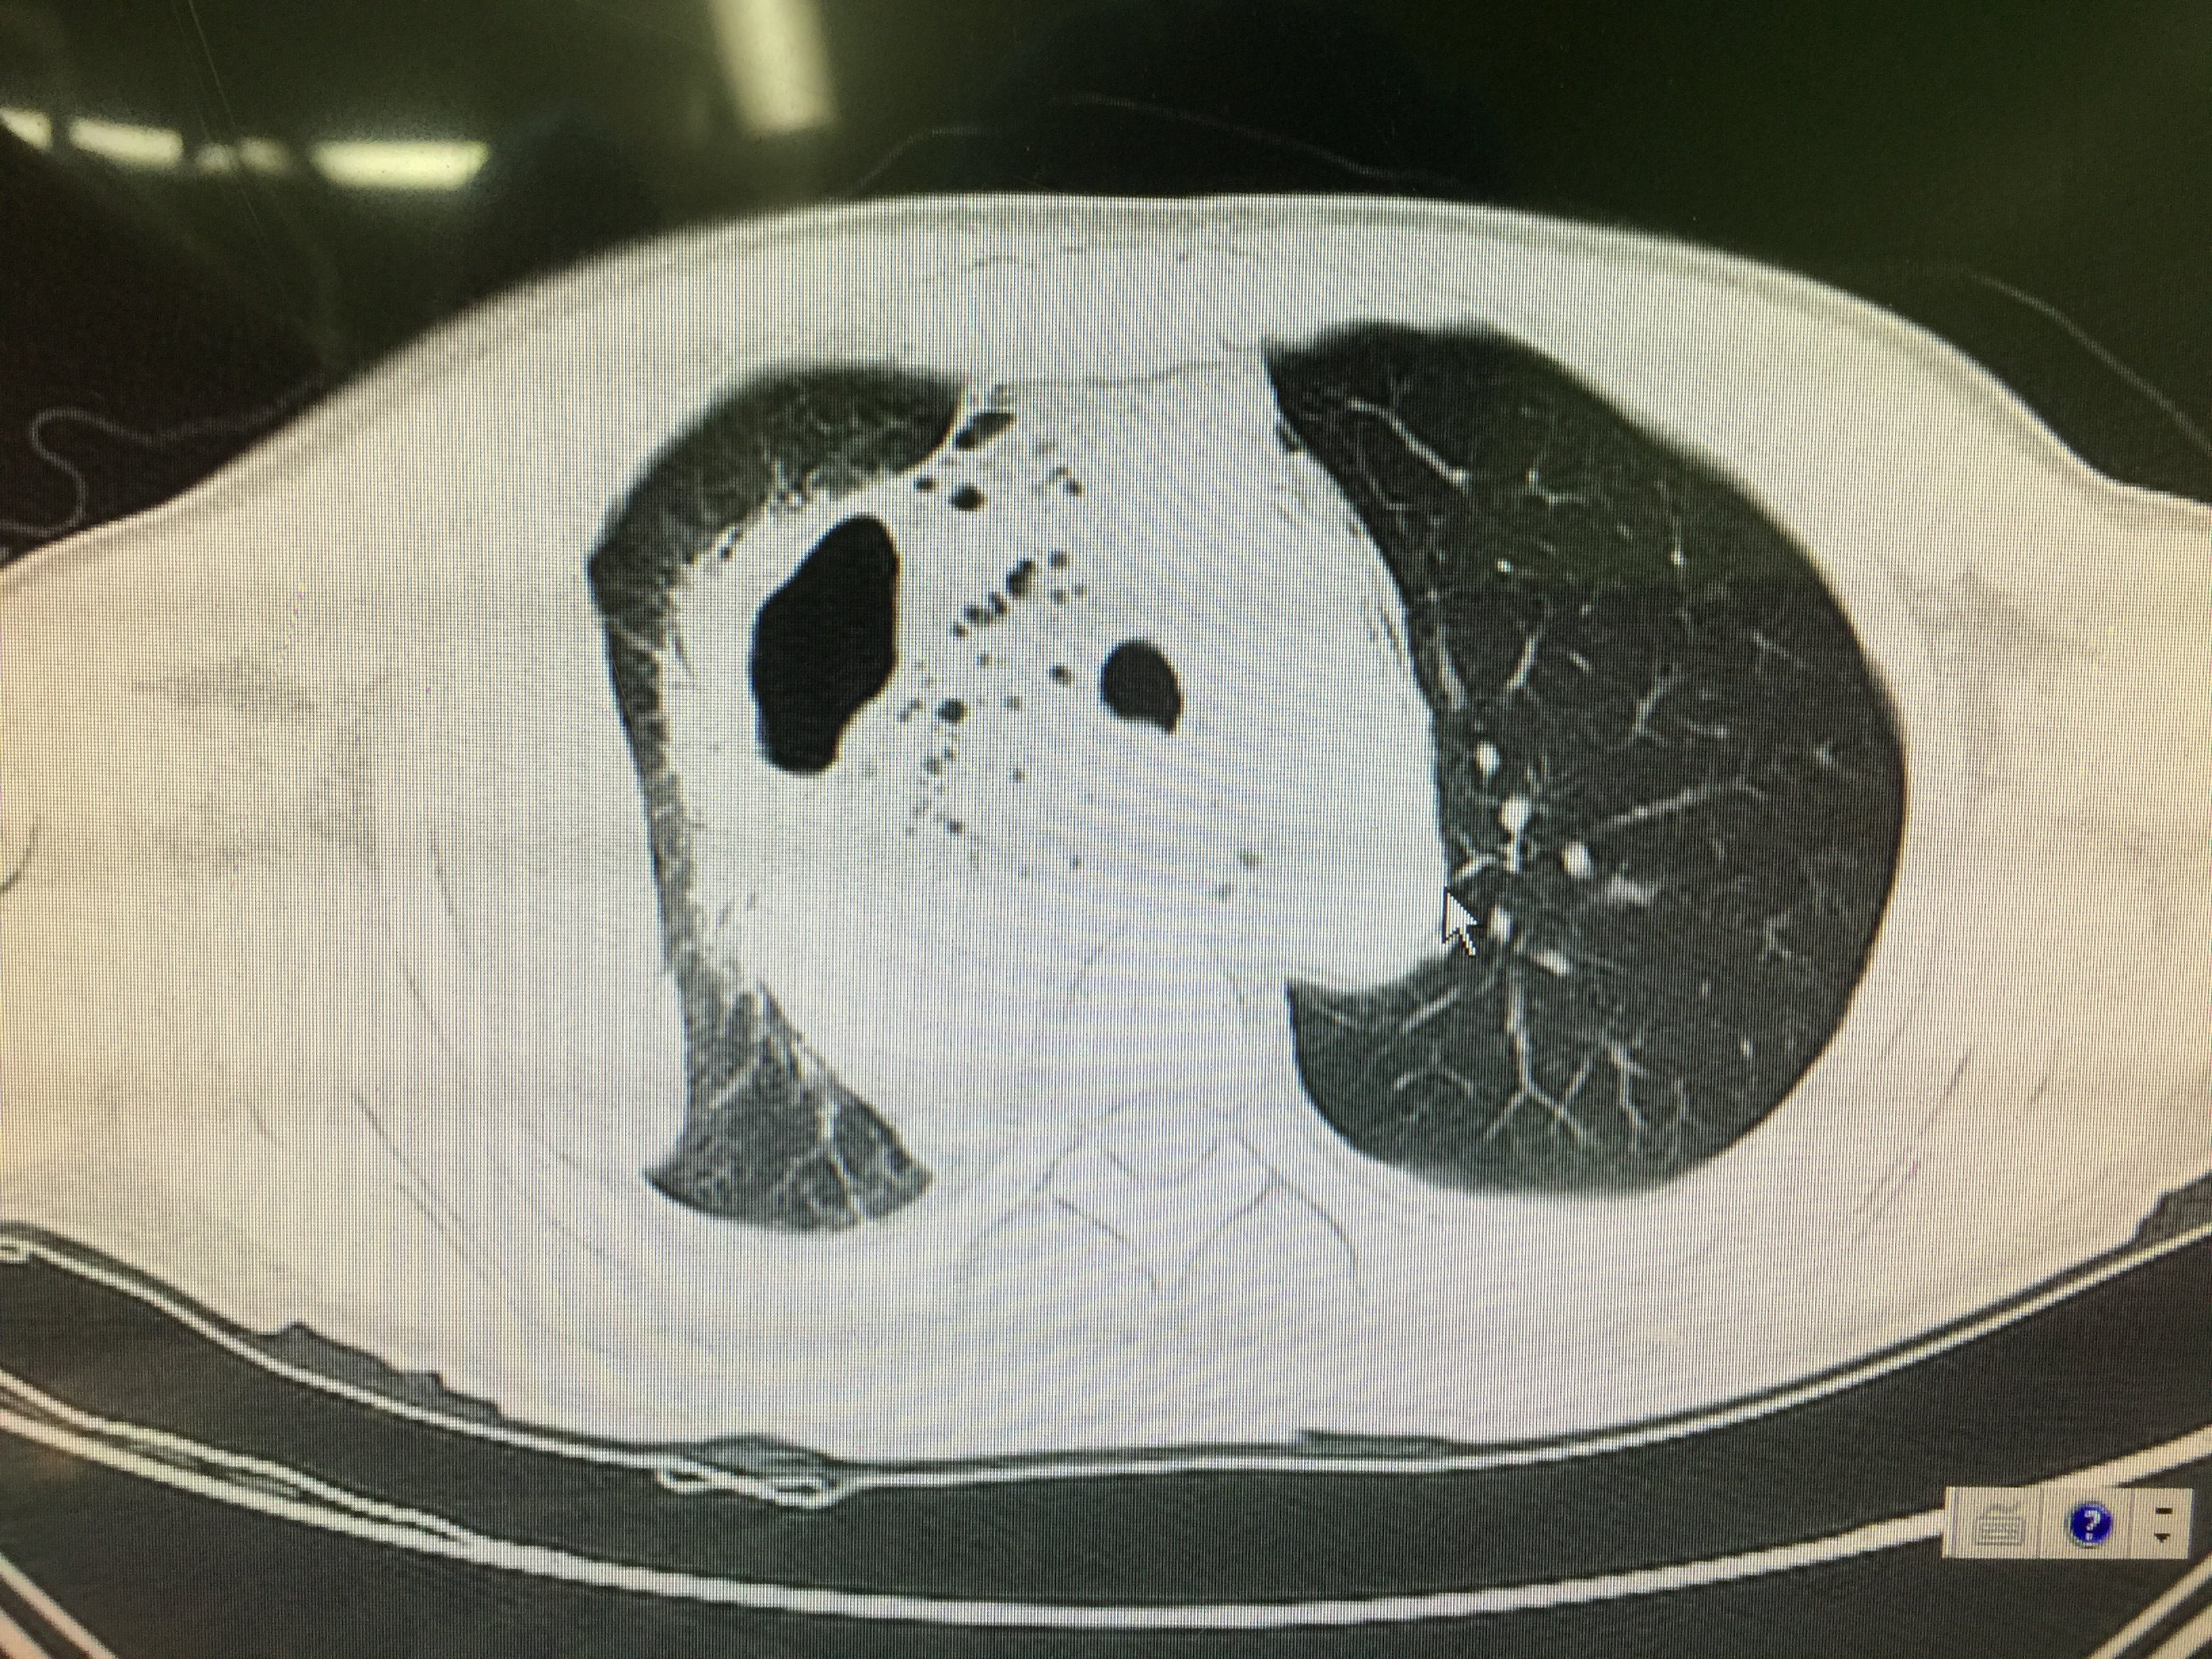

省立影像读片后纵隔肿瘤2009